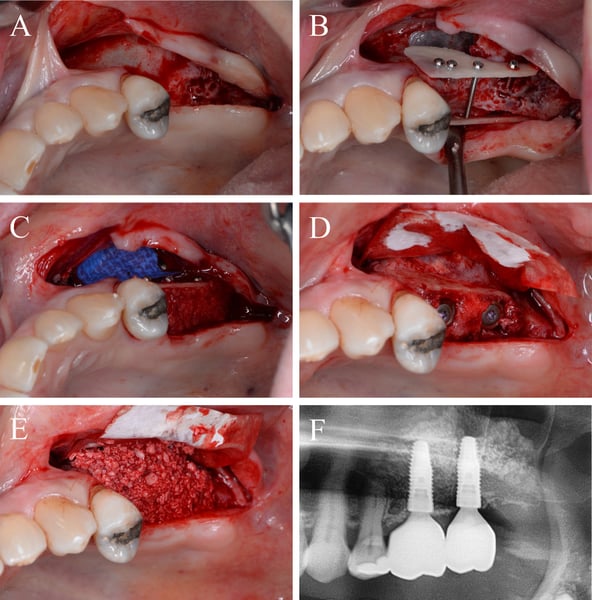

Figure 2.

Augmentation in the third quadrant with autogenous bone plates and autogenous bone chips using the shell technique. A, horizontal and vertical defect in the third quadrant after flap elevation. B, buccal and lingual autologous bone plates fixed with microscrews utilizing the shell technique. C, bony envelope filled with autologous bone chips collected during thinning process of the bone plates

Figure 3.

Augmentation in the fourth quadrant with allogeneic bone plates and autogenous bone chips using the shell technique. A, horizontal and vertical defect in the contralateral quadrant after flap elevation. B, buccal and lingual allogeneic bone plates fixed with microscrews utilizing the shell technique. C, bony envelope filled with autologous bone chips collected during thinning process of the autologous bone plates harvested in the third quadrant

Figure 5.

Implantation in the third quadrant and augmentative relining with bovine bone substitute material and collagen membrane.A, regenerated bone of the autologous bone plate site with only minor signs of resorption. B, situation after insertion of two bone level implants and fixation of a collagen membrane for the relining GBR. C, relining process finished with DBBM particles and membrane stabilized by resorbable sutures

Figure 6.

Implantation in the fourth quadrant and augmentative relining with bovine bone substitution material and collagen membrane. A, regenerated bone in the allogeneic bone plate site with only minor signs of resorption, as well. B, situation after insertion of two bone level implants and fixation of a collagen membrane for the relining GBR. C, relining process finished with DBBM particles and membrane stabilized by resorbable sutures